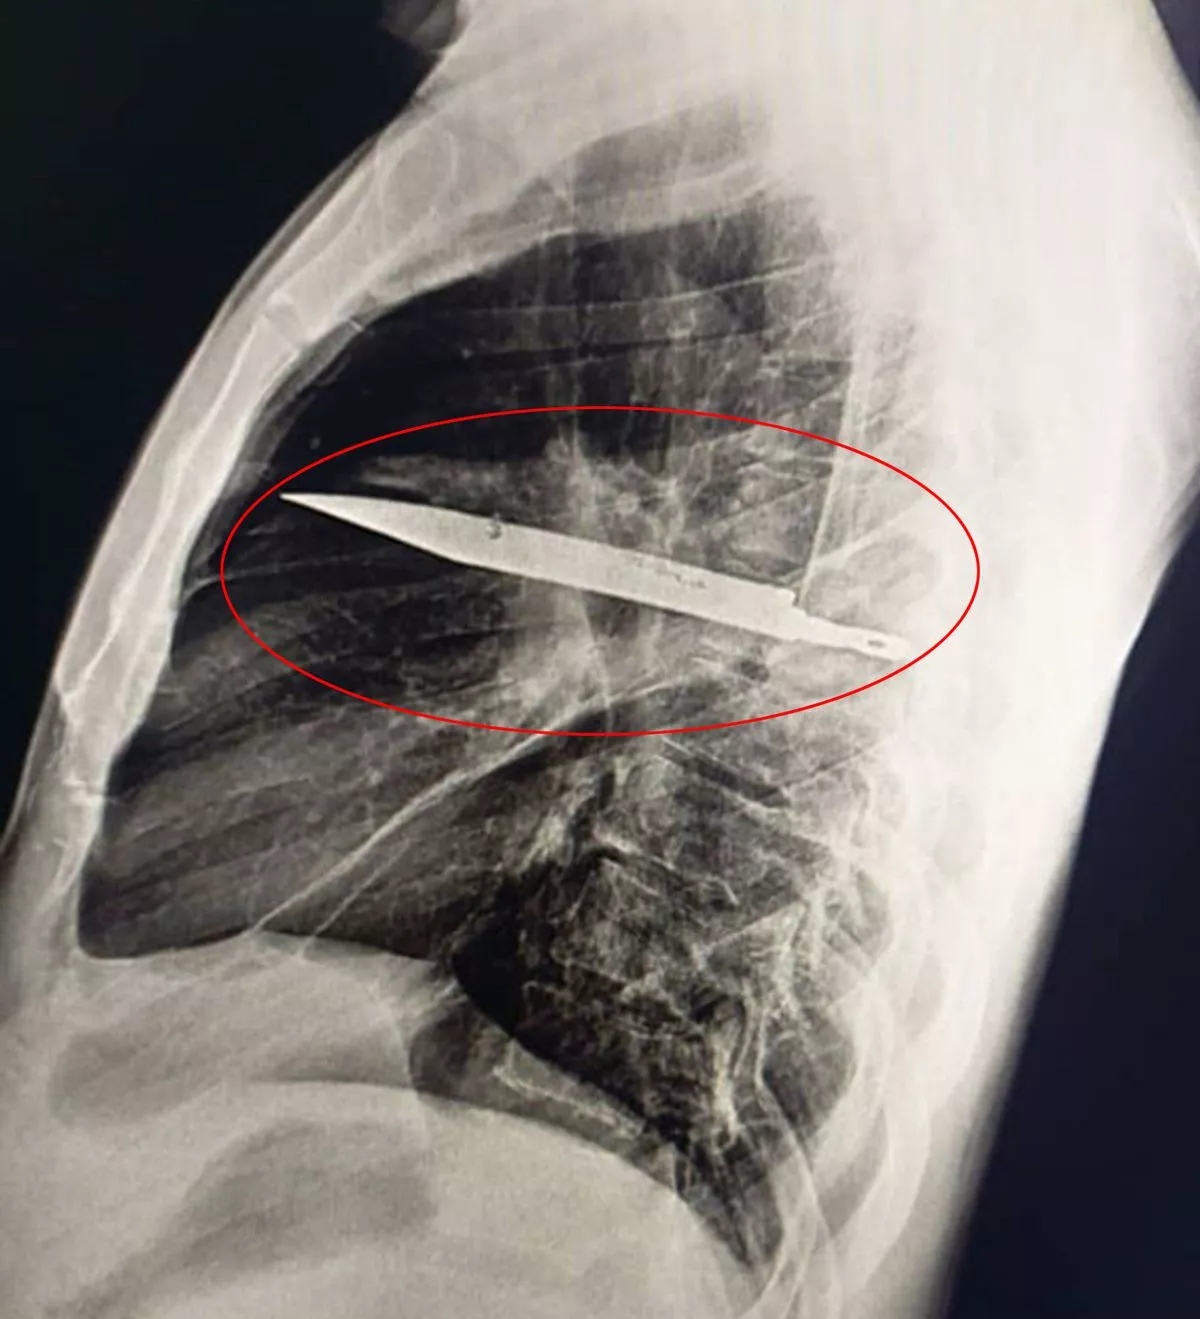

Các bác sĩ vô cùng kinh ngạc khi phát hiện một người đàn ông đã sống với một lưỡi dao lớn găm trong ngực suốt 8 năm.

Người đàn ông không hề biết con dao ở trong ngực mình. (Ảnh: Jam Press/Tạp chí báo cáo ca phẫu thuật)

Cuộc sống của anh "bình yên vô sự" kể từ đó, theo lời bệnh nhân, cho đến khi anh ấy nhận thấy mủ chảy ra từ dưới núm vú. Và rồi thật khó tin, một phim chụp X-quang ngực đã tìm ra nguyên nhân gây ra căn bệnh hiện tại của người đàn ông - một lưỡi dao lớn găm vào giữa ngực. Các bác sĩ có thể thấy con dao đã đâm xuyên qua xương bả vai phải và tránh được các cơ quan quan trọng.